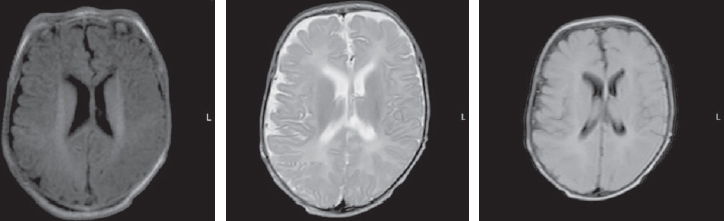

The differential diagnosis of paroxysmal conditions, as well as disorders of muscle tone (hypertension) in the neonatal period and in young children is quite complicated. Various states of the nervous system in newborns are transient and permanent, optimal and suboptimal, normal and pathological. Among them, we can mention non-epileptic paroxysmal states of early childhood. In some cases, non-epileptic paroxysmal states of early childhood is accompanied by motor disorders, manifested by an excessive increase in limb tone in newborns. This pathological condition of muscle tone in the English-language literature is referred to by the term stiffness baby (the syndrome of a “rigid” or “fettered” baby). Neonatal pathological muscle hypertonicity, unlike physiological hypertonicity of muscles of a newborn, is a rather rare condition. The article presents literature data and a description of the clinical observation of a patient with hyperekplexia. Hyperekplexia is a rare paroxysmal movement disorder in young children. The main clinical variants of the disease, methods of diagnosis and correction, the main mutations associated with this condition are considered. The article describes the own clinical observation of an early-age patient with hyperekplexia, its clinical picture, features of paroxysmal states and therapy, neuroimaging data, electroencephalographic phenomena recorded in the patient and genetic testing that confirmed the diagnosis of non-epileptic paroxysmal disorders. The child has a mutation in the ATAD1 gene associated with type 4 Hyperekplexia (618011).